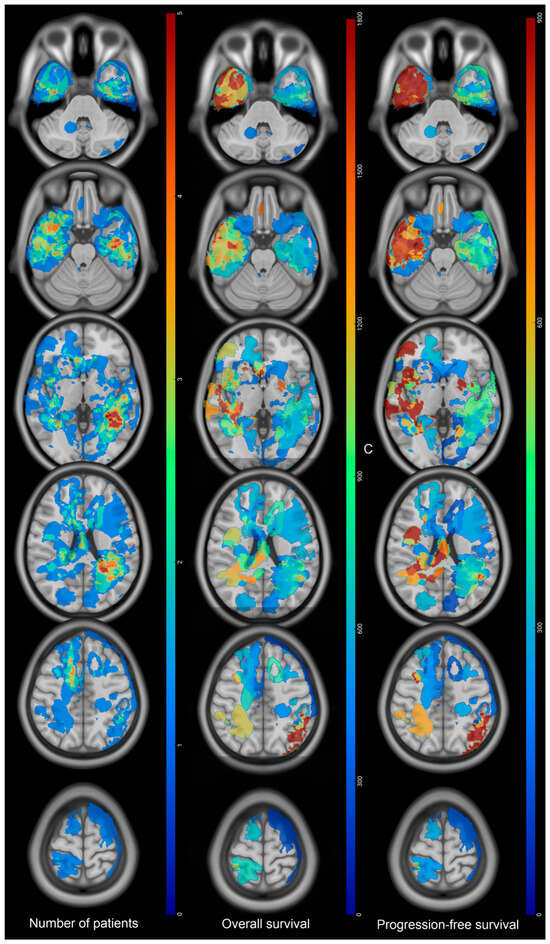

Prognostic Factors of IDH Wild-Type Glioblastoma After Extensive Surgery: A Multimodal Atlas of Tumor Locations, Recurrences and Management

by Hajar Selhane, Tiphaine Obara, Guillaume Vogin, René Anxionnat, Guillaume Gauchotte, Luc Taillandier, Marie Blonski and Fabien Rech

Cancers 2026, 18(1), 63; https://doi.org/10.3390/cancers18010063 - 24 Dec 2025

Introduction: Glioblastomas have poor prognosis despite aggressive treatment. Patterns of recurrence and overall survival (OS) can be very different. The population with complete resection having a so-called good prognosis can nevertheless present poor OS. Our purpose was to assess the OS and patterns [...] Read more.

Introduction: Glioblastomas have poor prognosis despite aggressive treatment. Patterns of recurrence and overall survival (OS) can be very different. The population with complete resection having a so-called good prognosis can nevertheless present poor OS. Our purpose was to assess the OS and patterns of recurrence thanks to multimodal statistical maps in glioblastoma with large extent of resection (residue < 10 mL). Methods: adult patients presenting IDH wild-type glioblastoma between 2013 and 2019 were selected. Clinical data and MRI characteristics were collected. Preoperative, postoperative, and recurrence volumes were segmented and normalized in the MNI space to compute statistical maps. Log-rank test and Cox model were used to assess OS and prognosis factors. Results: 60 patients were included. Mean residual volume was 0.89 ± 2 mL. Median OS was 22.3 months (95% CI: (20–35)). Initial location in the corpus callosum was associated with low OS (317 vs. 783 days, HR = 0.46, p = 0.003). At recurrence, KPS > 90 and tumor volume < 10 mL were associated with higher OS (p =0.006 and p = 0.05). Tumor contact with the SVZ as well as multifocal recurrence did not show any impact on the OS. Conclusions: High OS can be obtained thanks to surgery with residual volume < 10 mL. Invasion of the corpus callosum at diagnosis is associated with a poor prognosis despite a large extent of resection. Results suggest that large resection near the SVZ might decrease its putative influence on OS. Full article

Figure 1